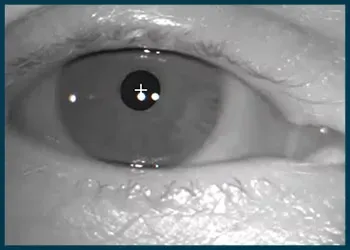

Bei einer monoculären Ableitung kann das zweite Auge nicht beurteilt werden. Somit können pathologische Pupillenbewegungen wie konvergenter oder divergenter Nystagmus oder andere pathologische Nystagmusformen oder Sakkaden des zweiten Auges nicht erkannt werden.